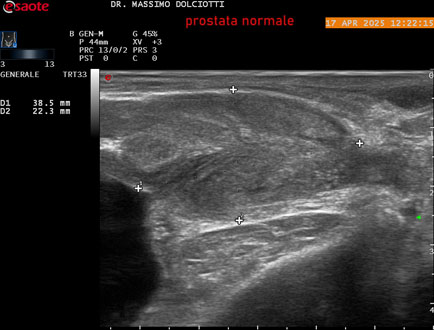

Data inserimento: 01/10/2025

Ecografia del: 17/04/2025

Strumento: Esaote MyLab Eight

Sonda: Convex Multifrequenza 1-8 MHz, Endocavitaria Multifrequenza 3-9 MHz e 3-13 MHz

Età Paziente: M 35 anni

Motivazione dell'esame: disuria.

Commento all'esame: le immagini ed il video documentano la prostata di ecostruttura regolare e morfovolumetria normale con diametro trasversale di 40 mm, diametro anteroposteriore di 21 mm e diametro longitudinale di 43 mm, con volume prostatico calcolato di 18 cc (v.n. < 20 cc), il profilo prostatico è regolare e netto, non si documentano calcificazioni intraghiandolari, la vascolarizzazione della ghiandola è normale. La vescicola seminale destra presenta diametro longitudinale di 44,4 x 7,8 mm, la vescicale seminale sinistra ha diametro longitudinale di 45,3 mm x 7,2 mm.

Conclusioni: prostata normale (normal prostate).